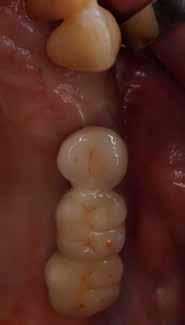

10. ábra: Lágyszövetek a hat hét gyógyulást követően.

11. ábra: Az elkészült híd a szájban – okkluzális nézet.